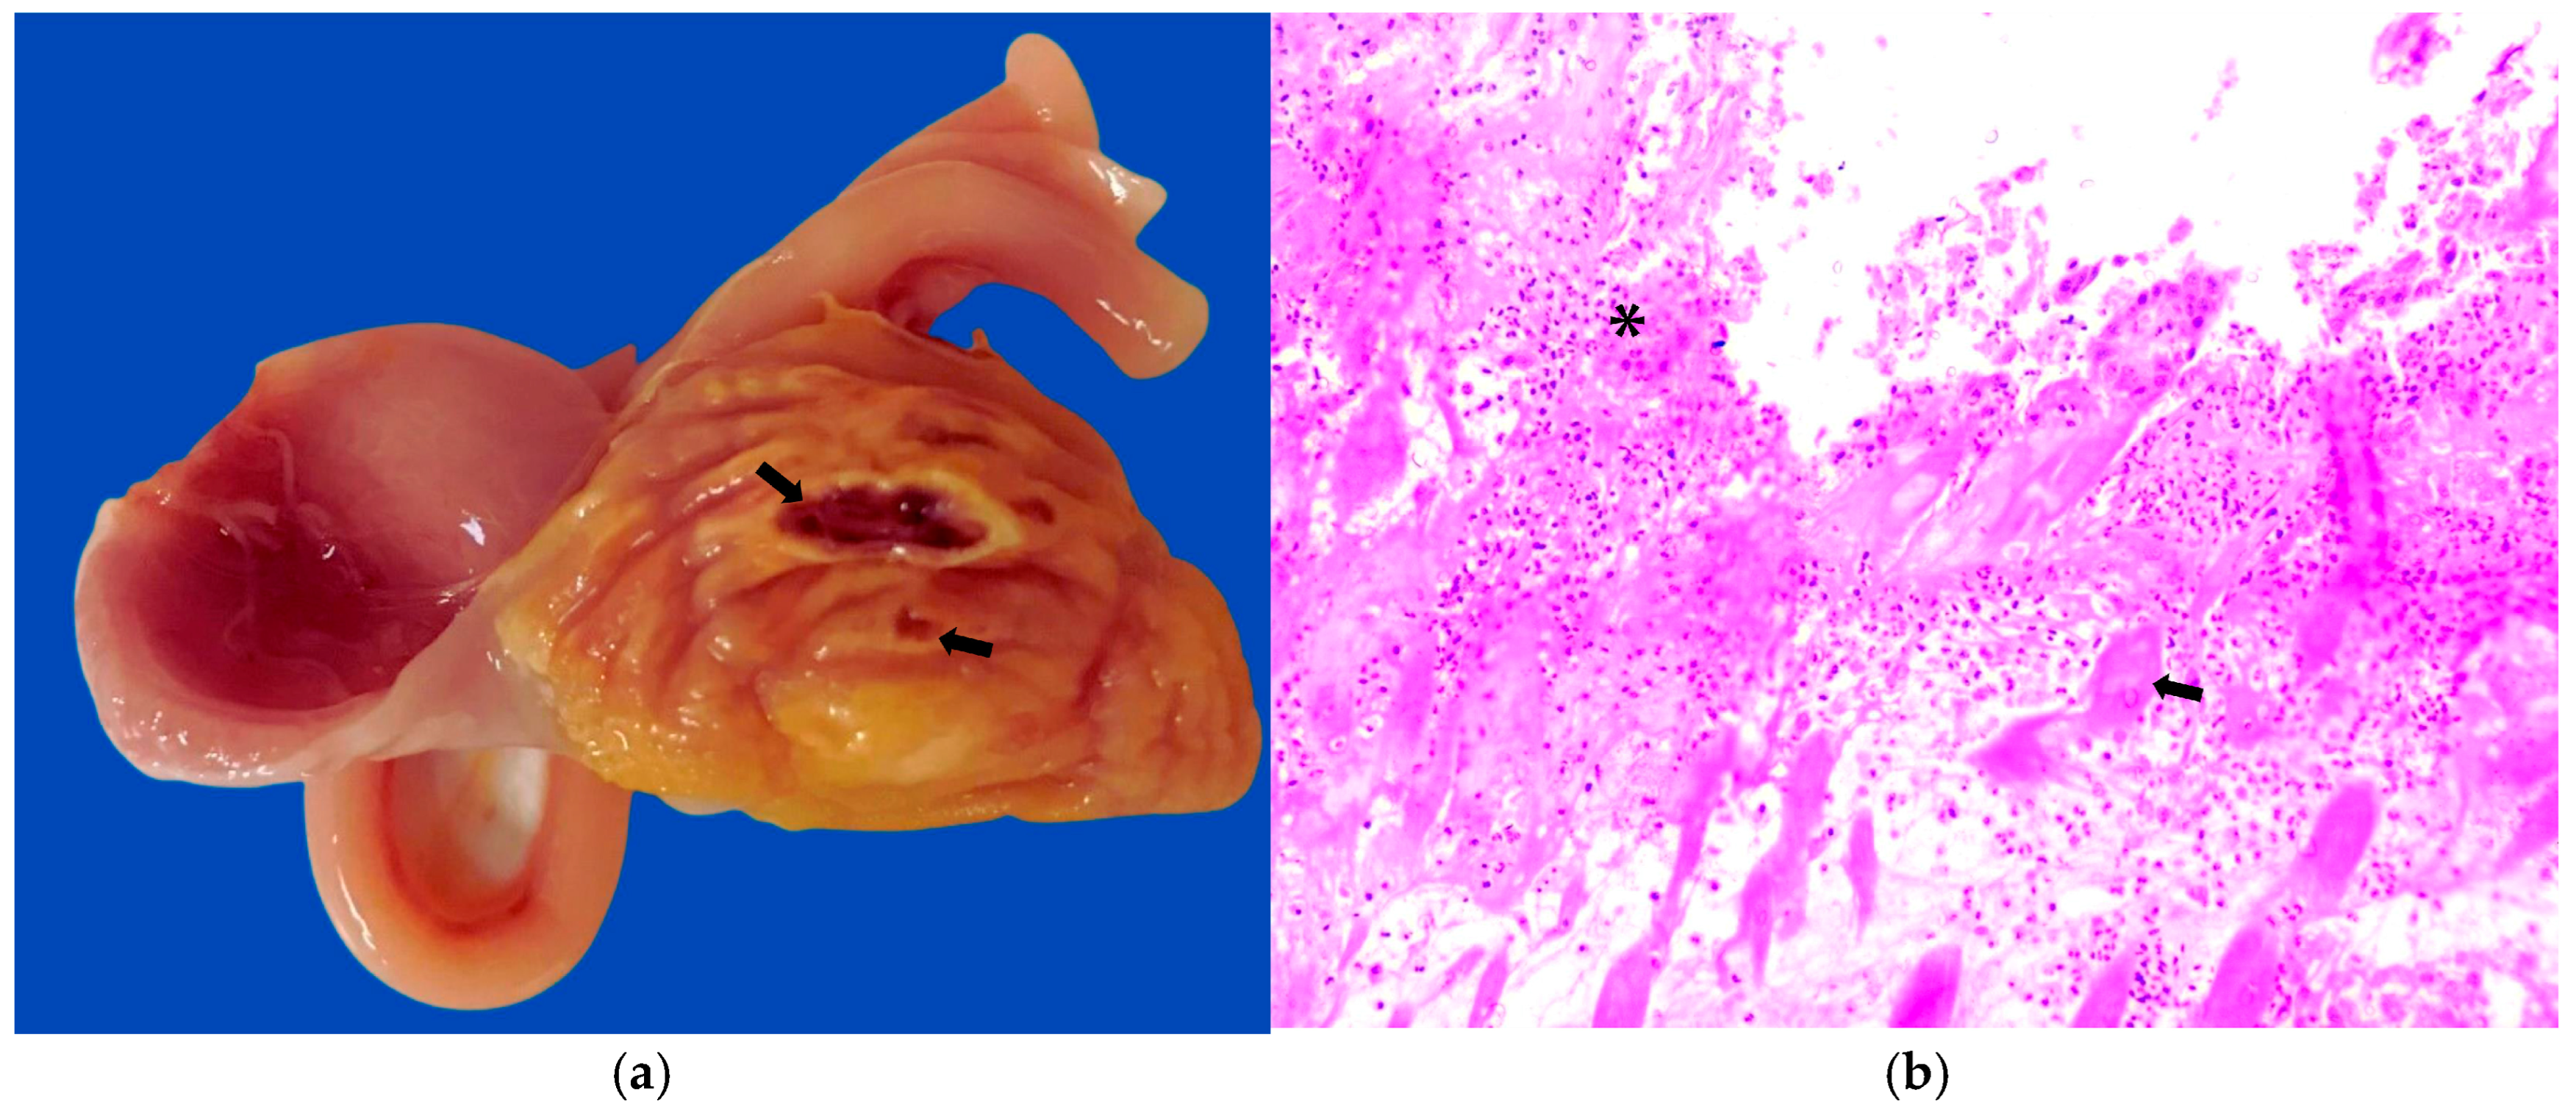

3.1. Gross and Microscopic Results